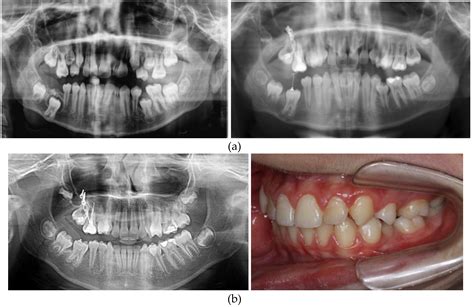

The diagnosis of a cancerous jaw tumor typically involves a combination of clinical examination, imaging studies, and biopsy. The diagnostic process may include:

• Clinical examination: A healthcare professional will examine the jaw and surrounding areas for any signs of swelling, tenderness, or abnormalities.

• Imaging studies: X-rays, CT scans, MRI, or PET scans may be used to visualize the tumor and determine its extent.

• Biopsy: A small sample of the tumor tissue is removed and examined under a microscope to confirm the presence of cancer cells.

In some cases, additional tests may be required to determine the stage of the cancer and whether it has spread to other parts of the body.